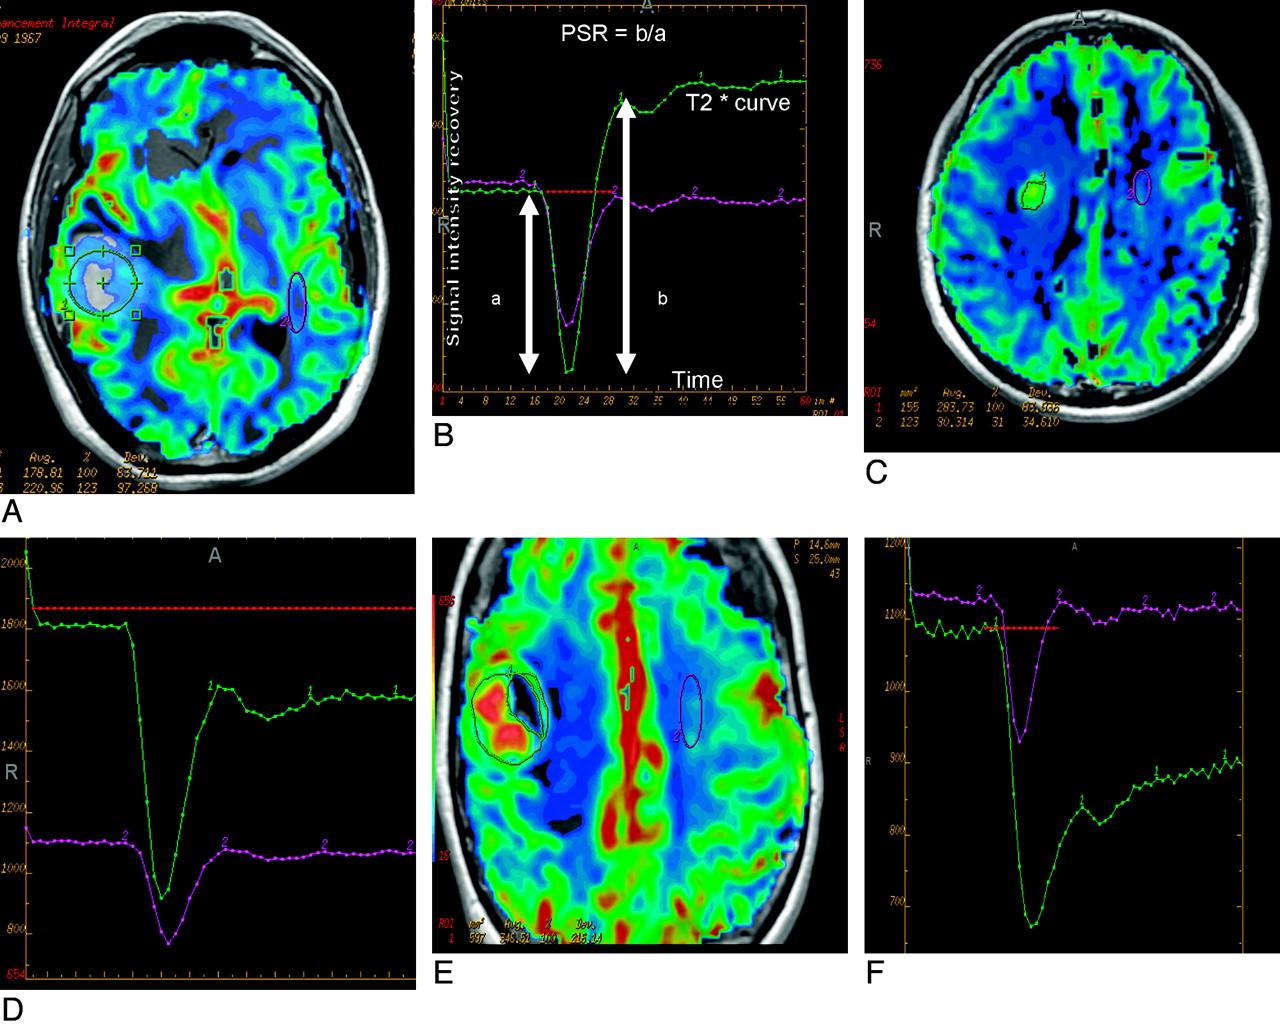

Signal-intensity curves and rCBV maps in the 3 different groups of lesions showed characteristic features, including significant overshoot with high max and mean PSR in lymphomas (Fig 1A), high rCBV and intermediate PSR in gliomas (Fig 1B), and low mean PSR in metastatic lesions (Fig 1C).

A and B, Perfusion maps overlaid on postcontrast T1-weighted image (A) in an enhancing mass lesion of the brain. The large green region of interest placed on the enhancing mass lesion to measure the mean signal-intensity recovery shows overshoot from baseline on the recovery maps (B). The lesion proved to be a lymphoma on histopathology. C and D, Perfusion maps overlaid on postcontrast T1-weighted image (C) in a mass lesion of the brain surrounded by significant edema, which proved to be GBM on histopathology. The large green region of interest placed on the enhancing mass lesion shows approximately 77% mean signal-intensity recovery on the recovery maps (D). E and F, Perfusion maps overlaid on postcontrast T1-weighted image (E) in an enhancing mass lesion of the brain. The large green region of interest placed on the enhancing mass lesion shows about 32% mean signal-intensity recovery on the recovery maps (F). The lesion proved to be a metastases on histopathology.